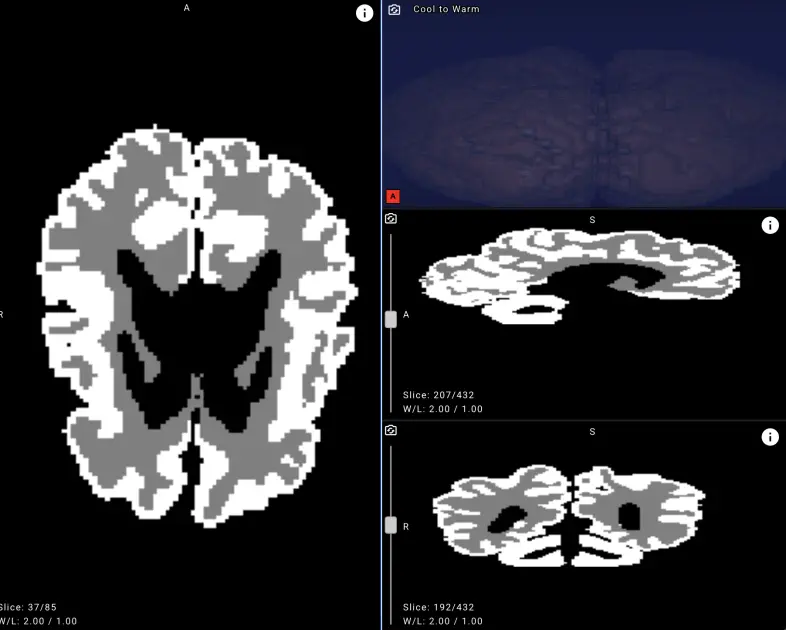

Ancak hastalığın yaşamın ilk yılında teşhis edilmesi oldukça zor. Bebek beyninin hızlı gelişimi ve MR görüntülerinde gri ve beyaz madde ayrımının zayıf görünmesi, radyologlar için tespit sürecini zorlaştırıyor. Bu noktada yapay zekanın görüntü analizi konusundaki gücü devreye giriyor. Yandex’in geliştirdiği model, bu ayrımı yüksek doğrulukla yaparak uzmanlara tanı koyma sürecinde objektif veriler sunuyor.

Yandex pediatrik sinirbilim konusunda uzman akademisyenlerle iş birliği yaparak geniş veri kümeleri üzerinde model eğitimi gerçekleştirdi. Açıklamalı veri setlerinin sınırlı olması, önceki araştırma girişimlerinde önemli bir sorun olarak öne çıkmıştı. Bu engelin aşılması için yeni anatomik segmentasyon verileri üretildi ve gelişmiş sinir ağı mimarileri kullanıldı. Sonuç olarak ortaya çıkan yapay zeka modeli, beyin MR’larında gri ve beyaz maddeyi ayrıştırma konusunda yüzde doksanın üzerinde doğruluk seviyesine ulaştı.